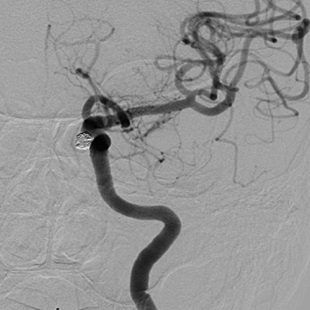

脳動脈瘤コイル塞栓術は、カテーテル(細いチューブ)を足の付け根の大腿動脈から挿入し、レントゲンで透視下にカテーテルを頚部の動脈まで誘導します。続いて、このカテーテル内にマイクロカテーテルと呼ばれる非常に細いチューブを通し、レントゲンで透視下に脳動脈瘤内まで誘導します。このマイクロカテーテルを通して塞栓物質(極めて細いプラチナ製コイル)を脳動脈瘤の中に詰め、脳動脈瘤内に血液が流れ込むのを遮断することで再破裂を予防します。

脳動脈瘤コイル塞栓術

脳動脈瘤の中にコイルをつめて、血液が流れ込まないようにする

血管内治療 脳動脈瘤コイル塞栓術

当科で治療した年々大きくなった大型脳底動脈瘤の3次元脳血管撮影像です。脳動脈瘤と周囲の血管の状態が非常によく分かるため、術前に十分な検討が可能でした。

術前

術後、脳底動脈瘤はコイルにより完全に塞栓され、正常の脳底動脈の血流は維持されている。